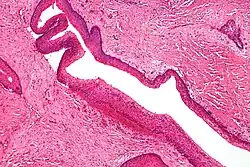

Intermediate magnification of an odontogenic keratocyst showing a folded cyst.

Intermediate magnification of an odontogenic keratocyst showing a folded cyst. -

Intermediate magnification of an odontogenic keratocyst

Intermediate magnification of an odontogenic keratocyst -